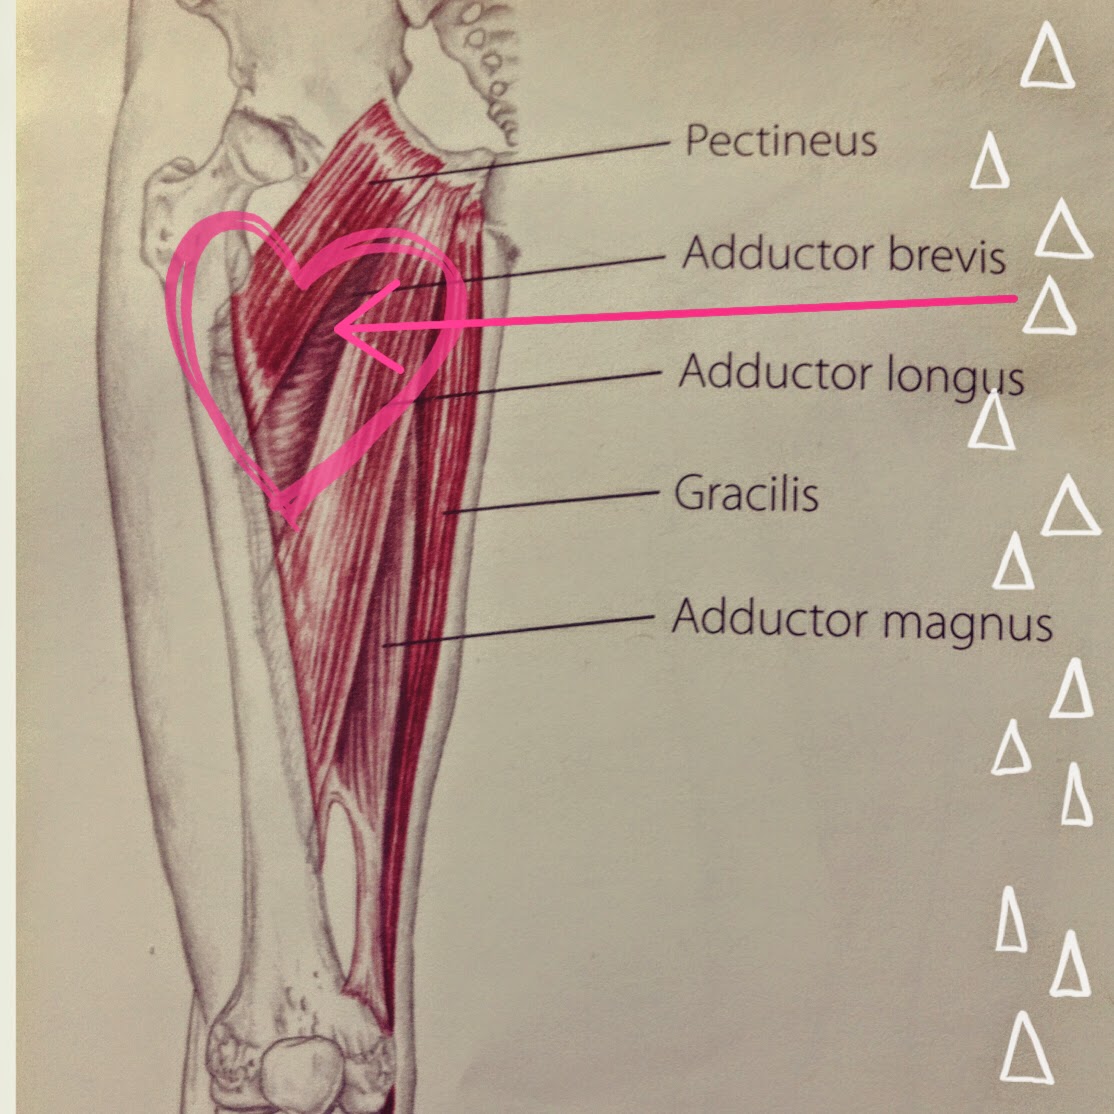

Анатомия и Функции Мышцы Adductor Magnus